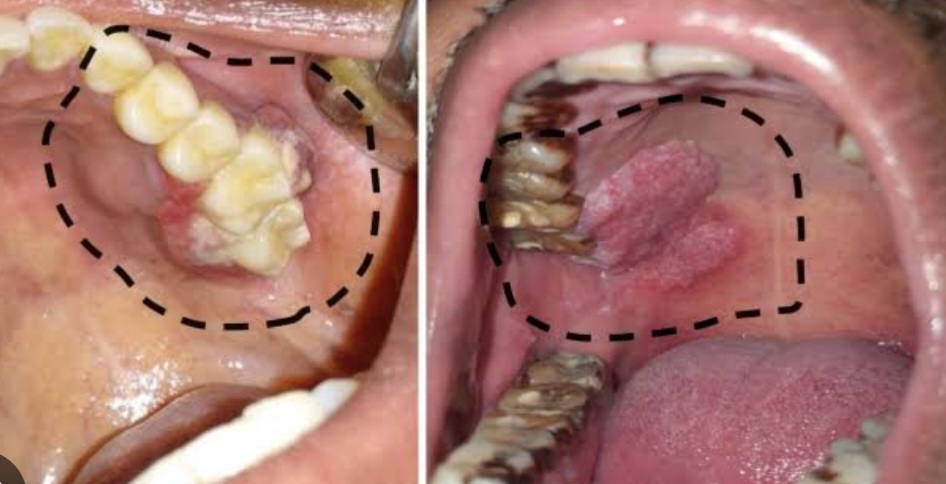

Mouth cancer (oral cancer) is due to uncontrolled growth of abnormal cells in the mouth, including the lips, tongue, gums, inner cheeks, roof, and floor of the mouth. Various risk factors are_ 1. Tobacco Use Smoking cigarettes, cigars, or hooka Chewing tobacco in the form of snuff, betel leaf 2. Alcohol Consumption alcohol usage increases the risk, especially when used with tobacco 3. Human Papillomavirus (HPV) Infection especislly HPV-16. 4. Poor Oral Hygiene & Dental Issues Chronic irritation due to ill-fitting dentures or rough teeth Poor oral hygiene 5. Excessive Sun Exposure _ causes lip cancer 6. Weakened Immune System 7. Unhealthy Diet Low intake of fruits and vegetables and high intake of spicy food can contribute to cancer risk. 8. Genetic Factors 9. Exposure to Certain Chemicals Exposure to asbestos, formaldehyde, or other carcinogens to people working in industry and factory may increase risk. For those experiencing chronic sore throat , oral ulcers, mouth (oral )cancers , hoarsness of voice iand for treatment solutions in Mumbai, or voice care , throat care near me, Dr. Sheetal Radia Head and Neck Cancer surgeon provides expert Mouth and throat care with a personal approach. Recognized among top ENT doctors in Mumbai, Dr. Radia’s clinic offers advanced diagnostic tools and treatments for voice hoarseness, throat infection relief, oral , throat and neck cancers and more, designed for each patient’s unique needs. .